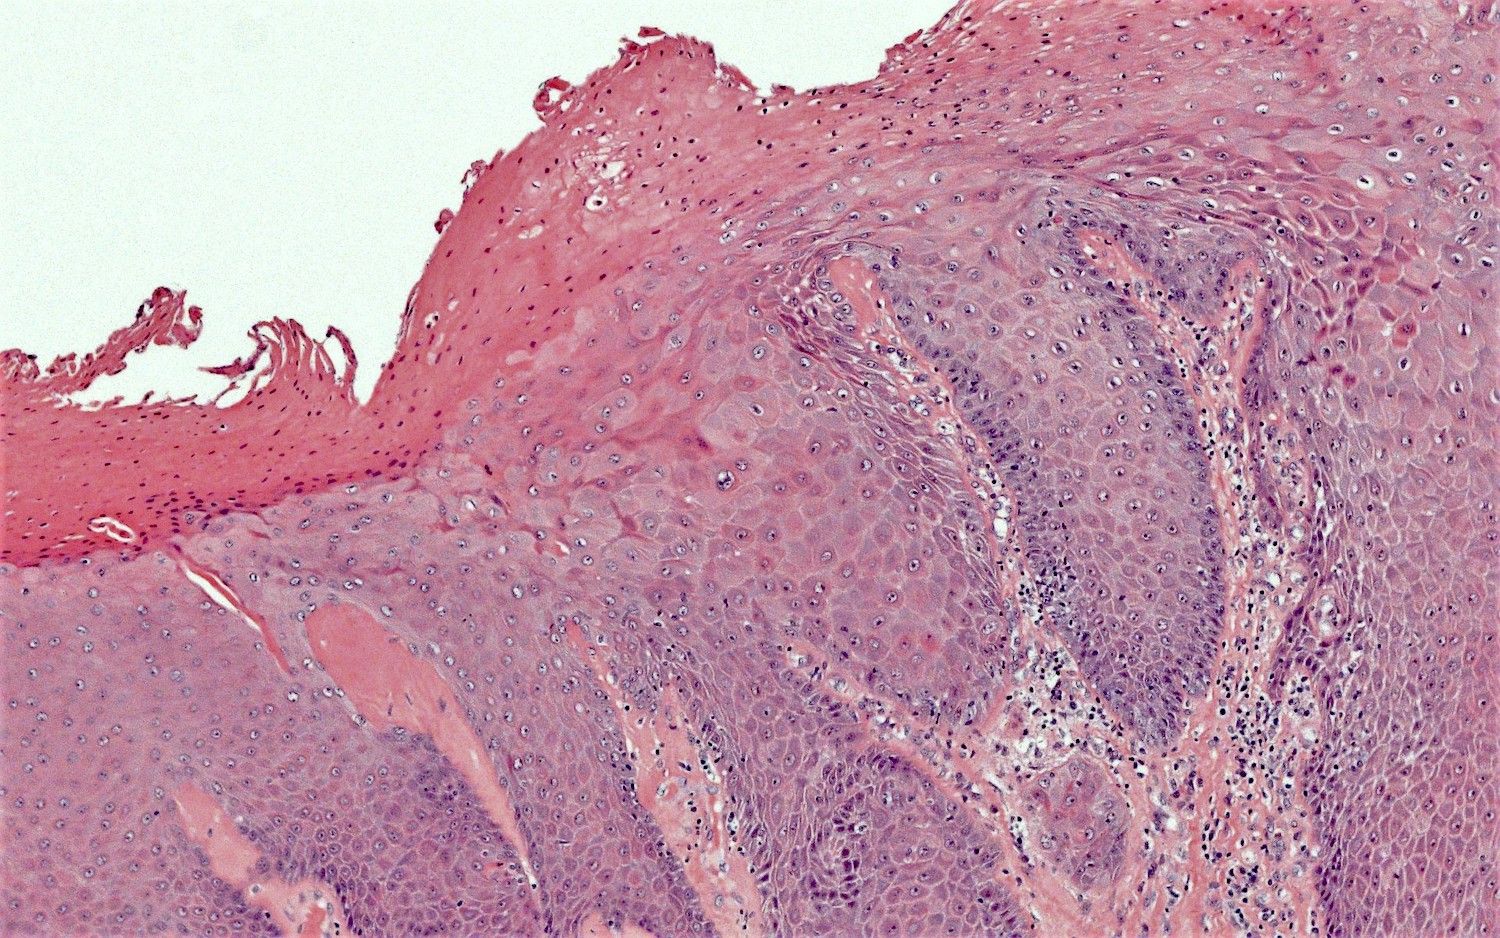

- Vacuolar interface reaction pattern in conjunction with dermal sclerosis (homogenized and hyalinized eosinophilic collagen bundles) of any thickness intervening between inflammatory infiltrate and epithelium or vessel walls (Mod Pathol 1998;11:844)

- Severe hyperkeratosis; thin epidermis, loss of rete pegs, basal cell degeneration, homogenized band of dense fibrosis at papillary dermis, upper dermal edema, band-like chronic inflammation

- In early stages, findings are subtle and often more prominent in adnexal structures than in interfollicular skin; adnexal structures show acanthosis, luminal hyperkeratosis and hypergranulosis

Microscopic (histologic) images

- HPV independent vulvar intraepithelial neoplasia (VIN):

- Other terminology: differentiated VIN (dVIN), differentiated exophytic vulvar intraepithelial lesion (DEVIL), vulvar acanthosis with altered differentiation (VAAD), vulvar altered maturation (VAM)

- Shows epithelial hyperplasia and loss of normal maturation; often shows significant basal atypia and may show mutant pattern p53 immunostaining (Mod Pathol 2011;24:297)